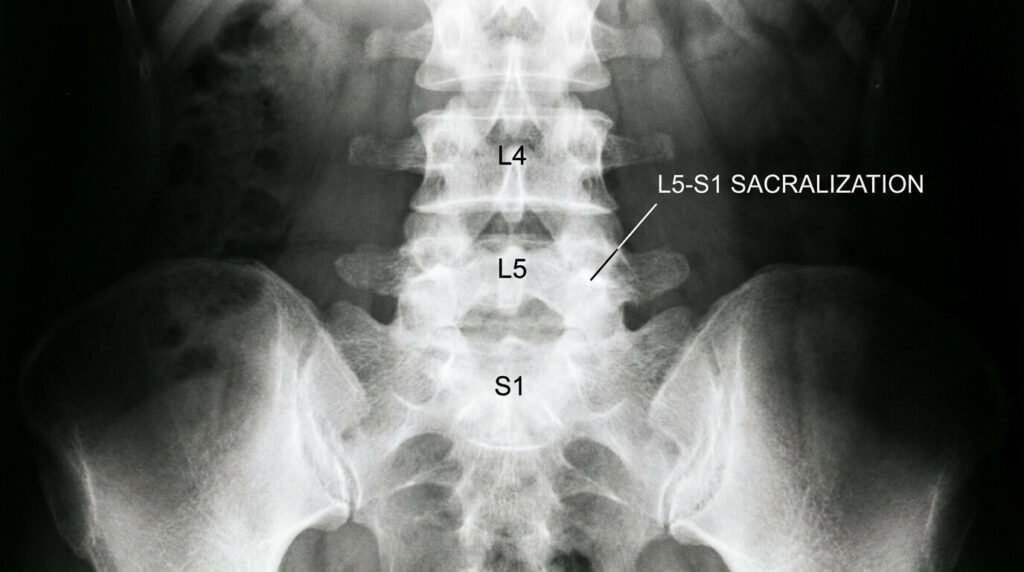

Radiographie du bas du dos montrant une vertèbre L5 fusionnée avec le sacrum (sacralisation), une anomalie transitionnelle fréquente

Vous avez passé une radiographie pour des douleurs lombaires persistantes et le compte-rendu mentionne une « sacralisation de la cinquième vertèbre lombaire (L5) ». Ce terme barbare peut effrayer, laissant imaginer une maladie osseuse grave ou dégénérative. En réalité, la sacralisation de L5 est une anomalie congénitale (de naissance) relativement fréquente, touchant environ 10 à 20% de la population. Elle signifie simplement que la dernière vertèbre lombaire a fusionné, partiellement ou totalement, avec le sacrum, devenant ainsi solidaire du bassin. Si elle passe souvent inaperçue, elle peut, dans certains cas, être la cause de douleurs mécaniques intenses et atypiques, regroupées sous le nom de Syndrome de Bertolotti. Faut-il opérer ? La kiné suffit-elle ? Quelles sont les options thérapeutiques pour vivre sans douleur avec cette colonne vertébrale « spéciale » ?

• 🦴 Une particularité anatomique : La sacralisation n’est pas une maladie, c’est une variante anatomique. La vertèbre L5 possède une apophyse transverse trop grande qui touche ou fusionne avec l’os sacré.

On classe ces anomalies selon la classification de Castellvi (du type I simple élargissement au type IV fusion complète). Les types intermédiaires (fusion incomplète) sont souvent les plus douloureux car il reste un micro-mouvement irritant.